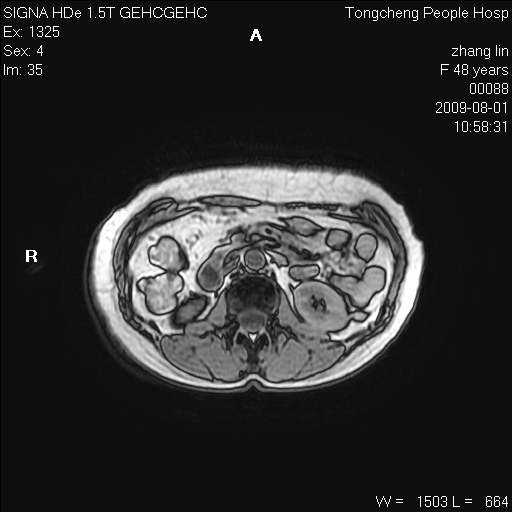

女,48岁。健康体检,彩超发现右肾占位性病变。平素健康。

临床诊断:右肾占位性病变,性质待定(囊肿?肿瘤?)。

上中腹部mr平扫+增强扫描,图像如下:

右肾上极见一类圆形病灶,t1wi呈等信号t2wi呈等高混杂信号,三期增强无强化,边界清---考虑囊肿出血。

同反相位均表现为等信号,病变无强化,考虑含蛋白的囊肿可能,弥散加权相或许有些帮助,

肝囊肿

慢性胆囊炎